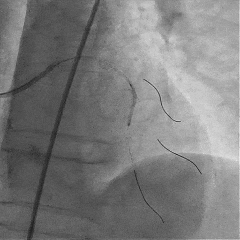

双侧造影,观察闭塞起始位置、长度、走行等

尝试通过RCA-圆锥支侧枝逆向开通LAD :

微导管辅助下,用SUOH03导丝尝试送入侧枝

经微导管TIP injection可见侧枝重度迂曲

侧枝重度迂曲,反复尝试未能通过

对角支送入IVUS导管,在IVUS实时指引下用尝试穿刺闭塞段

导丝未能进入闭塞段,导丝进入间隔支

逆向造影指引下继续尝试穿刺闭塞段

导丝远端与逆向造影不重叠,未在血管真腔

反复调整导丝最终进入D2#,可见导丝远端与D2侧枝重叠,证明远端位于真腔

微导管交换工作导丝至D2#远端

双腔微导管辅助下,导丝在逆向造影指引下成功通过LAD闭塞段,逆向造影显示导丝走行于LAD真腔内

交换工作导丝至LAD远端

预扩球囊依次扩张LAD近中段病变处,造影可见远端血管显影,导丝位于真腔。